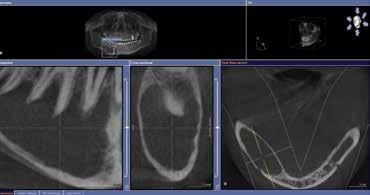

That TV was fine then, but could give up my 50” LED now? No way! For almost two years we have enjoyed the use of a GALILEOS 3D CT in Laguna Beach, and nowadays there’s no way I could give that up, either!

The day of the install, my team watched in eager anticipation as the technicians completed their work. Then our Sirona rep asked for a volunteer to be the first scan. We gave the honor to a team member and watched anxiously as the computer digested the information. It presented us with 3D images of her skull, and then I saw it… Hold on… That looks like a cyst!

Here are two other cases from September:

1) Idiopathic Dentigerous Cyst

The patient was a 16-year-old female who was asymptomatic and in good health. The cyst traveled from distal #32-#27 and was very expansive. It is currently being treated by decompression/marsupialization following extraction of tooth #32. Upon opening the lesion, the surgeon remarked that the mandibular nerve was just hanging in hollow space.

2) Massive Bone Loss and Sinus Floor Perforation resultant from Failing RCT #15

This patient was also asymptomatic and received a routine pre-surgical scan on the day of an anterior implant treatment with our periodontist. Even more intriguing, two years prior, this 80-year-old male had a sudden onset of severe pneumonia through the lungs to the plural space, requiring external drainage and six weeks of intravenous antibiotics. Medical doctors were not able to discover the source of the illness. On extraction, tooth #2 was very green, suggesting pseudomonas. The patient is now healing and reports he is “feeling great.”

Our team feels that we saved the first patient from certain future mandibular fracture, a problematic and unsatisfactory outcome, and likely a lifetime of unilateral mandibular and lingual numbness. We also suspect that we added years to the second patient’s life.

Since that first day, we have steadily discovered many infections and pathologies that we would have missed without our Cone Beam. Additionally, it makes all our surgical procedures safer and more predictable. Our GALILEOS is as crucial to our office culture as our CEREC® unit, because we all know that it allows us to provide better care for our patients.

Asymptomatic cyst never detected despite full orthodontic treatment and associated radiography.